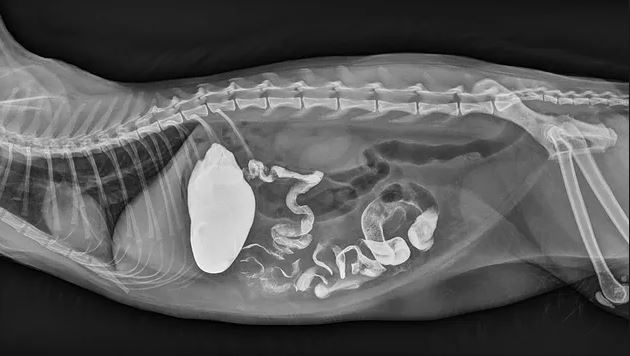

Contrast Radiography (Barium Contrast Study)

- Retrograde administration of positive, negative or a combination of contrast agents into the large intestine provides information about the intestinal lumen. Typical contrast studies performed at WestVet include myelogram, fistulogram, cystourethrogram, intravenous pyelogram, and upper GI barium series.

- Suspected large intestinal obstruction, eg colonic mass / foreign body

- Suspected intussusception Intussusception.